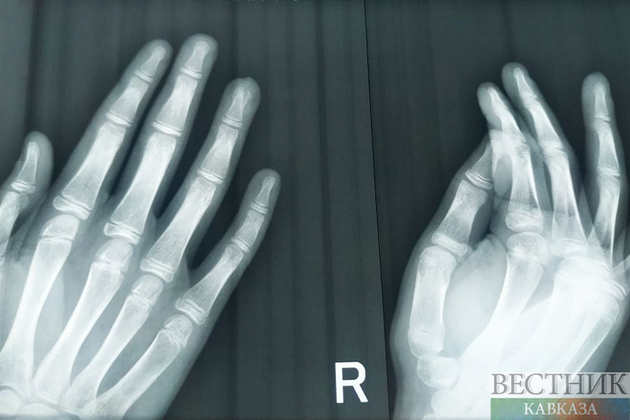

Скоро больницы КБР будут оснащены современным рентген-аппаратом с управлением на расстоянии. Его начали производить на одном из местных заводов.

Производством современных рентген-аппаратов «Парус» занялись в Кабардино-Балкарии. Они имеют возможность дистанционного управления, рассказал руководитель сервисной службы завода «Севкаврентген – Д» Владислав Занозин.

«Рентгеновский аппарат с дистанционным управлением предназначен для исследований в травматологии, ортопедии, хирургии и реанимации. Он хорошо подходит для лечебных учреждений, полевых медицинских пунктов, а также для массовых обследований населения»

Он подчеркнул, что аппарат позволит медикам эффективнее держать на контроле состояние пациента, не находясь при этом с ним в одном помещении.